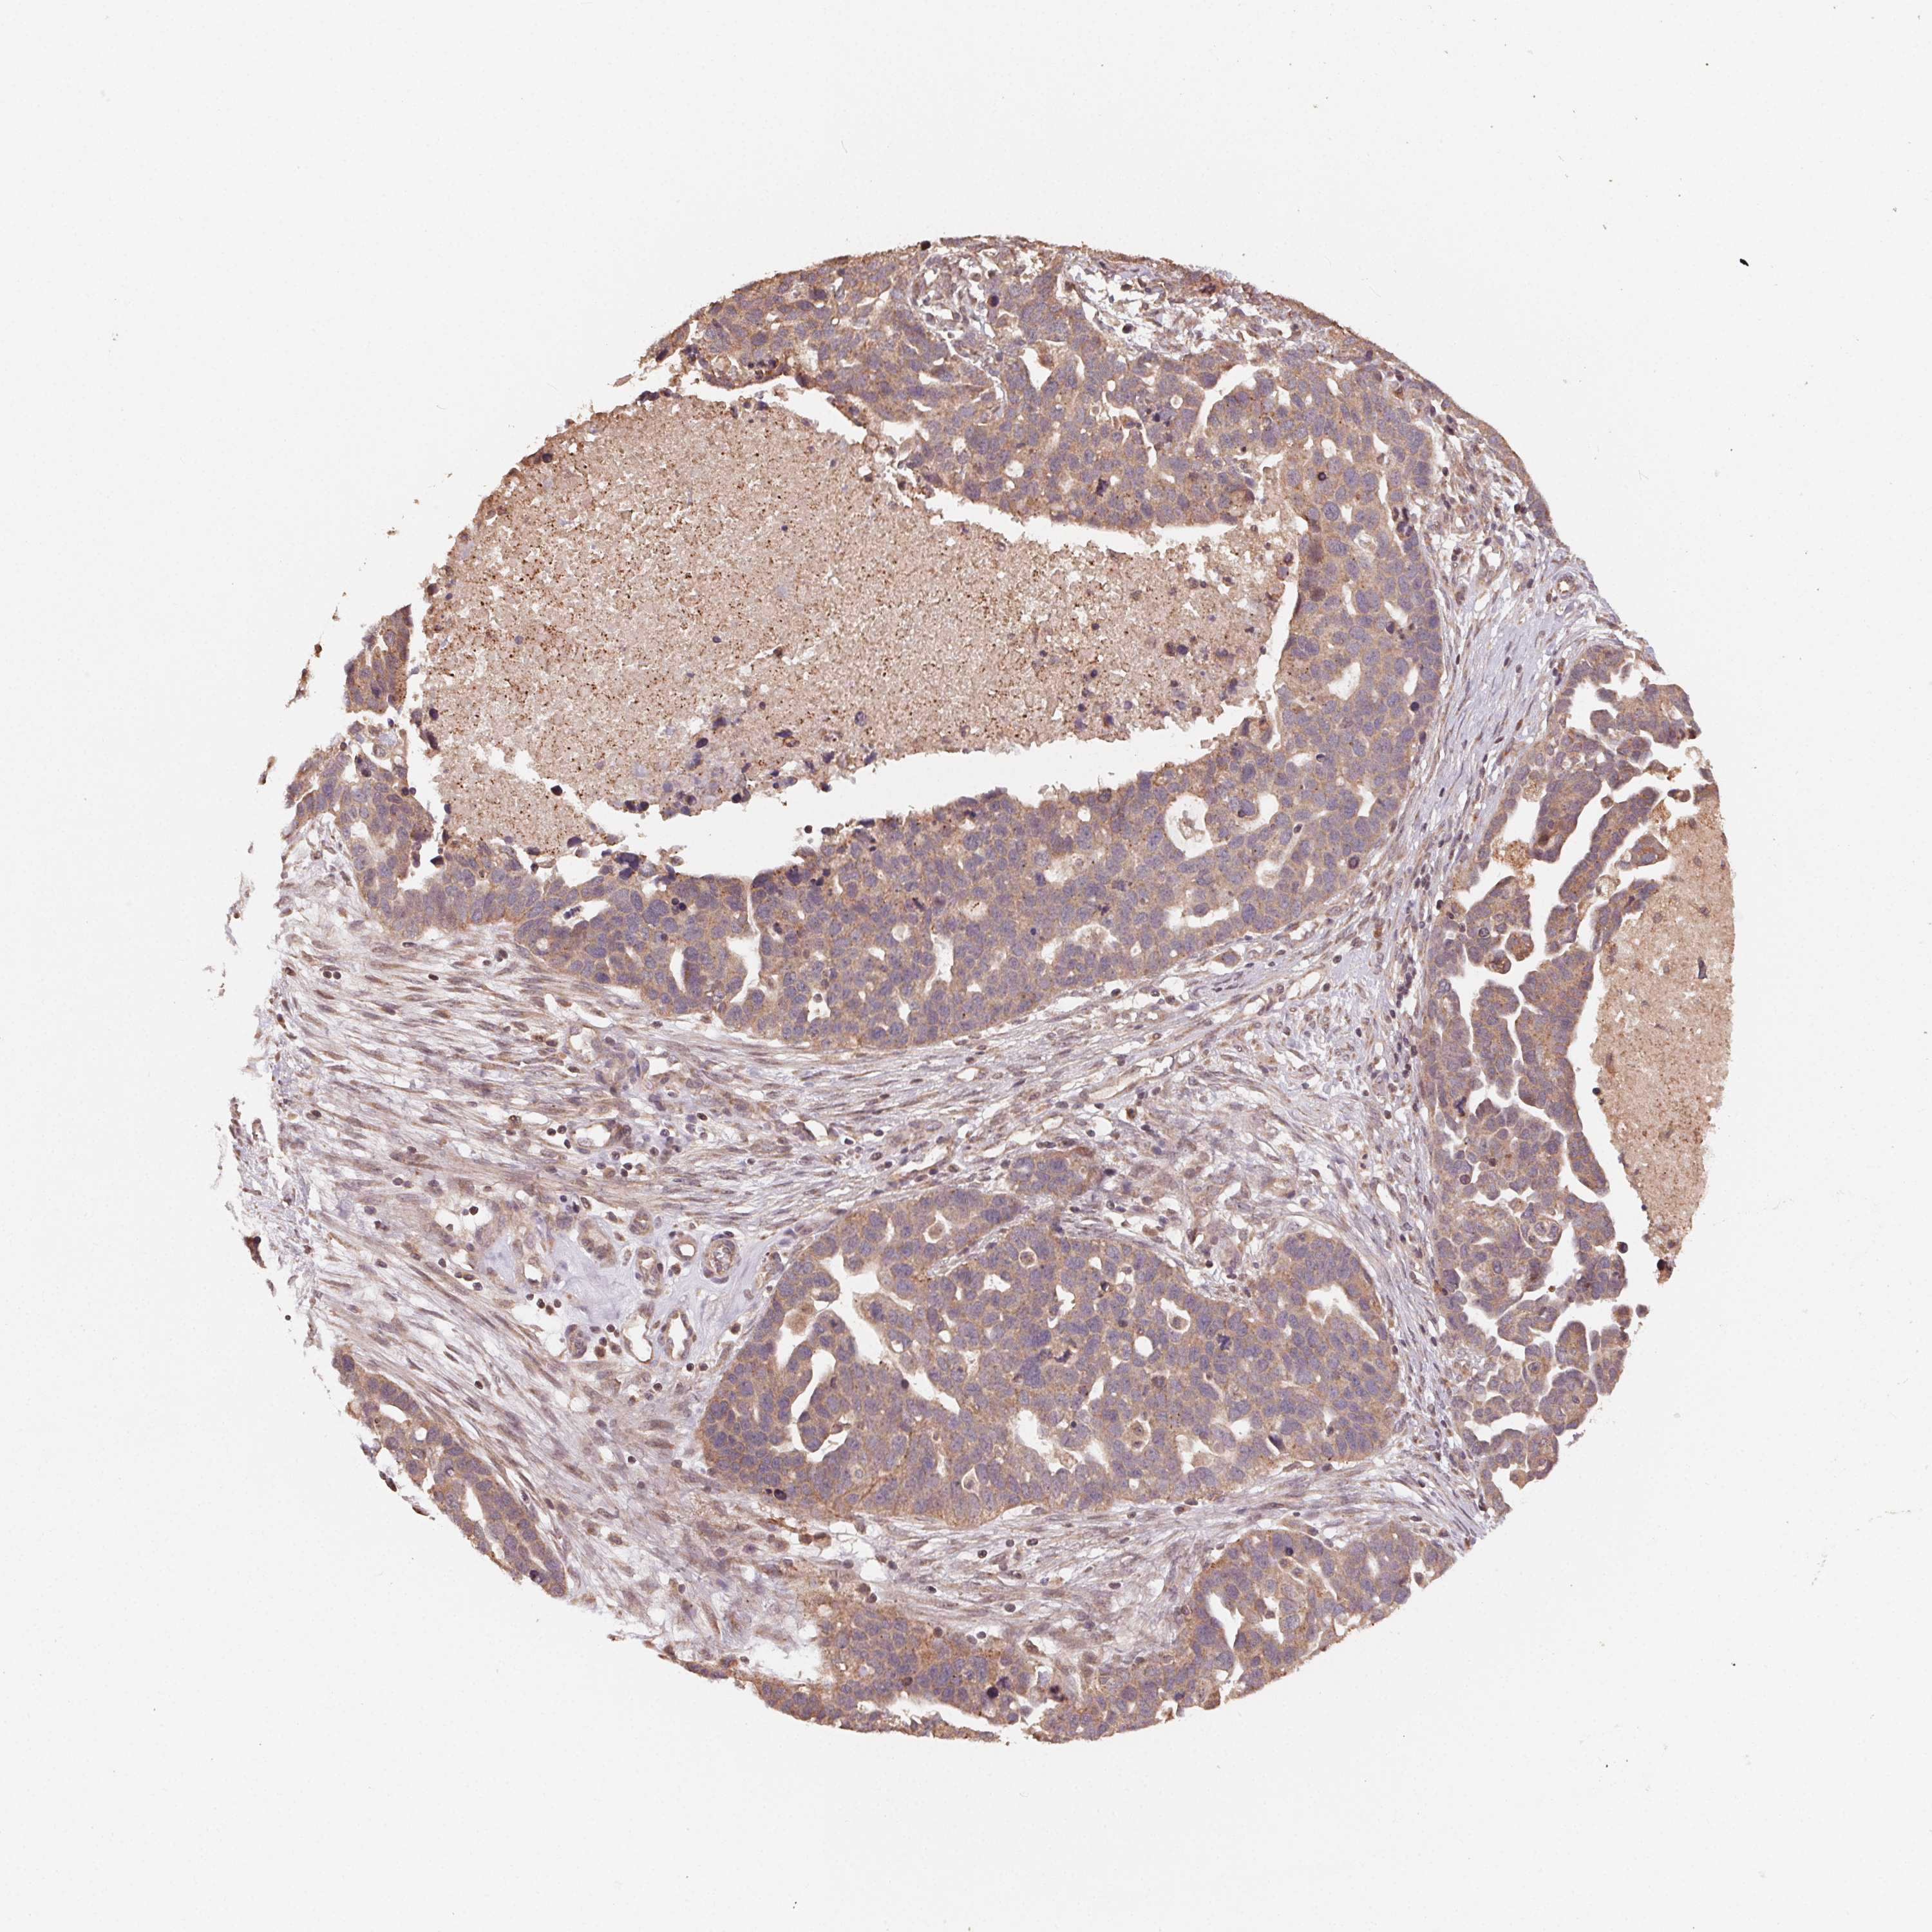

OVARIAN CANCER - Protein expressioni

A mouse-over function shows sample information and annotation data. Click on an image to view it in a full screen mode. Samples can be filtered based on level of antibody staining by selecting one or several of the following categories: high, medium, low and not detected. The assay and annotation is described here.

Note that samples used for immunohistochemistry by the Human Protein Atlas do not correspond to samples in the TCGA dataset.

Antibody stainingi

Antibody staining in the annotated cell types in the current human tissue is reported as not detected, low, medium, or high, based on conventional immunohistochemistry profiling in selected tissues. This score is based on the combination of the staining intensity and fraction of stained cells.

Each image is clickable and will lead to virtual microscopy that enables deeper exploration of all samples and also displays staining intensity scores, fraction scores and subcellular localization as well as patient and tissue information for each sample.

Antibody HPA065682

Staining

High

Medium

Low

Not detected

Intensity

Strong

Moderate

Weak

Negative

Quantity

>75%

75%-25%

<25%

None

Location

Nuclear

Cytoplasmic/membranous

Cytoplasmic/membranous,nuclear

Cystadenocarcinoma, serous, NOS

Cystadenocarcinoma, mucinous, NOS

Carcinoma, endometroid